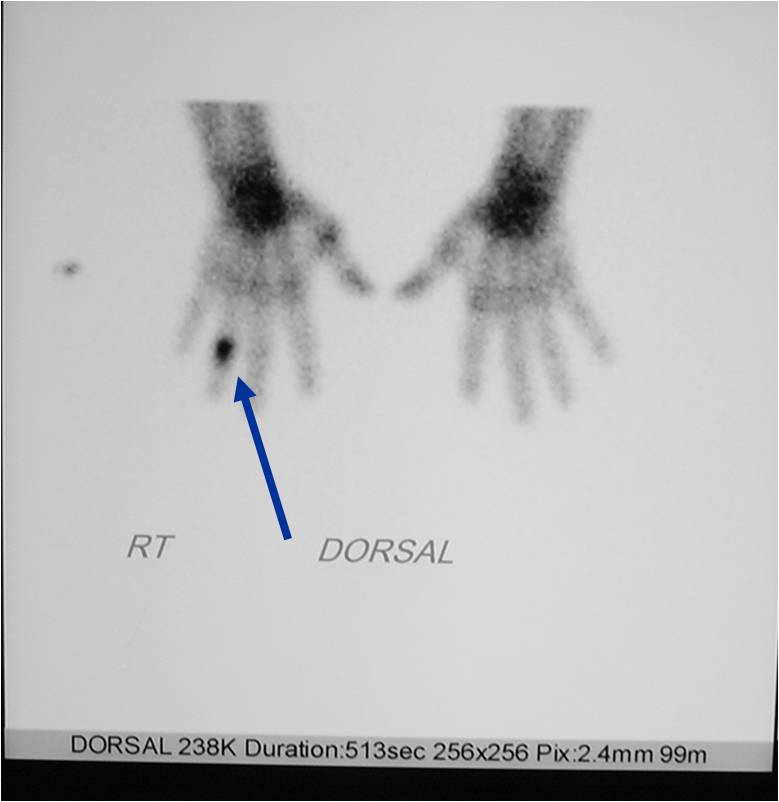

- 50% involve hands and feet (mostly phalanges)

- Cortex may be scalloped and thinned in the phalanges

Geographic Lesion Bony Expansion Minimal Calcification Some Enchondromas do not calcify

Geographic lesion Stippled calcifications in lesion Phalanx is expanded Significant endosteal scalloping No cortical destruction No soft tissue extension Cortex Scalloped and Expanded